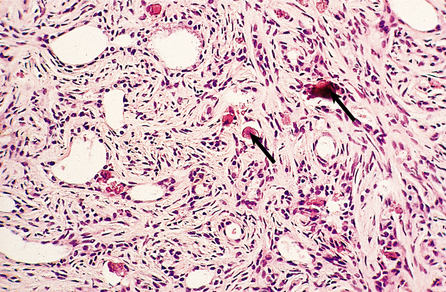

Sclerosing adenosis

In sclerosing adenosis there is lobular proliferation but the acini become distorted. The proliferation involves both epithelium and myoepithelium, but the latter tends to predominate. Large amounts of collagen can intervene between the glandular components, although the extent of this varies both within the same breast and between patients (Fig. 18.9). Due to the collagen component these lesions can mimic carcinomas clinically, and on mammograms where the associated calcification can be seen.

image

Fig. 18.9 Sclerosing adenosis. There are glandular structures with intervening cords of cells in a fibrous stroma. Areas of calcification (arrowed) are also present; these would render the lesion visible on mammography.